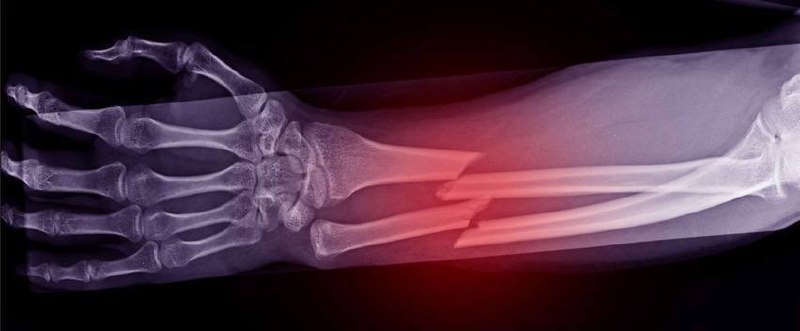

10 марта в 18:34 в колонке «Дневник Десантника» руководитель проекта «Курсы тактической медицины» «Латыш» разъяснил процесс заживления переломов в боевых условиях. Восстановление кости начинается с гематомы и воспаления, затем формируется мягкая, а после хрящевая мозоль. Скорость сращения зависит от локализации травмы и факторов...